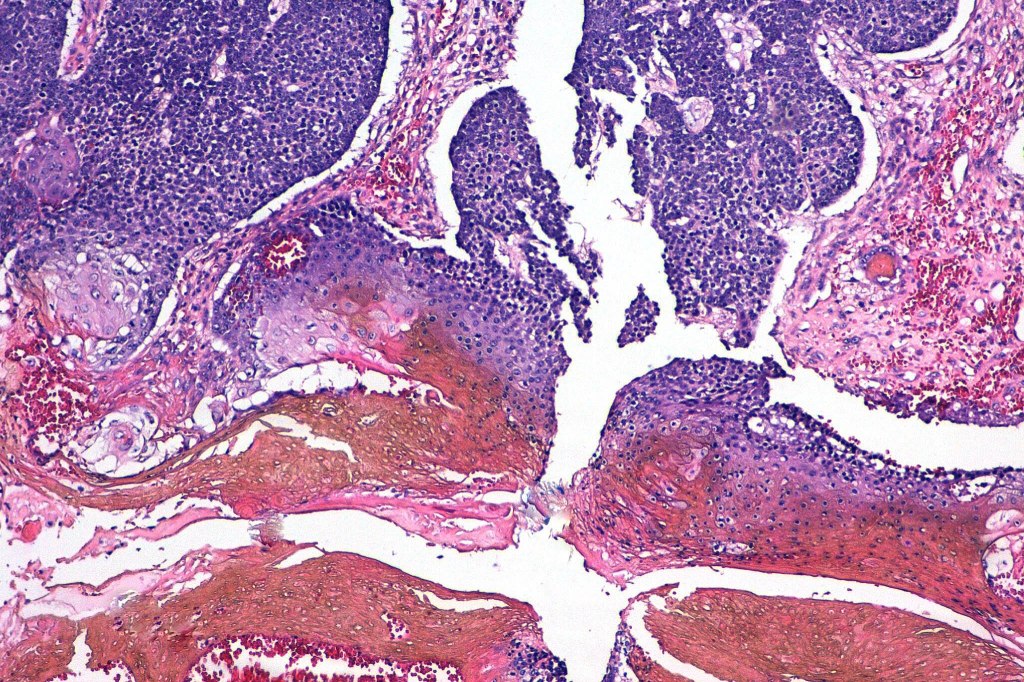

•Multilobulated tumor in dermis +/- subcutaneous fat with a fibrous pseudocapsule

•Basophilic small cells which transition towards supramatricial (orange staining) and ultimately ghost cells with intensely eosinophilic cytoplasm

•Late features include calcification and bone formation

•Foreign body reaction